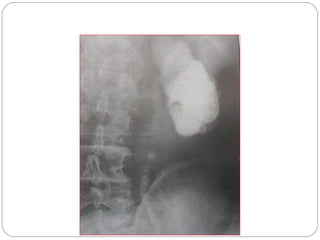

Horseshoe kidney

Kidneys placed lower than

normal

Malrotation of pelvis

Lower pole calyces of both

sides deviated towards

midline

Ureters have characteristic

vaselike curve

Pelvicalyectasis

Renal calculi

Intravenous urogram (IVU)

shows an altered renal axis

with medially directed lower

renal poles, which suggests

horseshoe kidney. Also note

the dilated collecting system of

the left kidney, resulting from

a uretero pelvic junction

obstruction; this is a frequently

associated finding